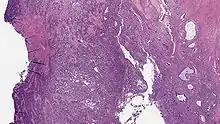

Micrograph of a low-grade endometrial stromal sarcoma. H&E stain.

Low-grade endometrial stromal sarcoma

Low-grade endometrial stromal sarcoma consists of cells resembling normal proliferative phase endometrium, but with infiltration or vascular invasion. These behave less[3] aggressively, sometimes metastasizing, with cancer stage the best predictor of survival. The cells express estrogen/progesterone-receptors.